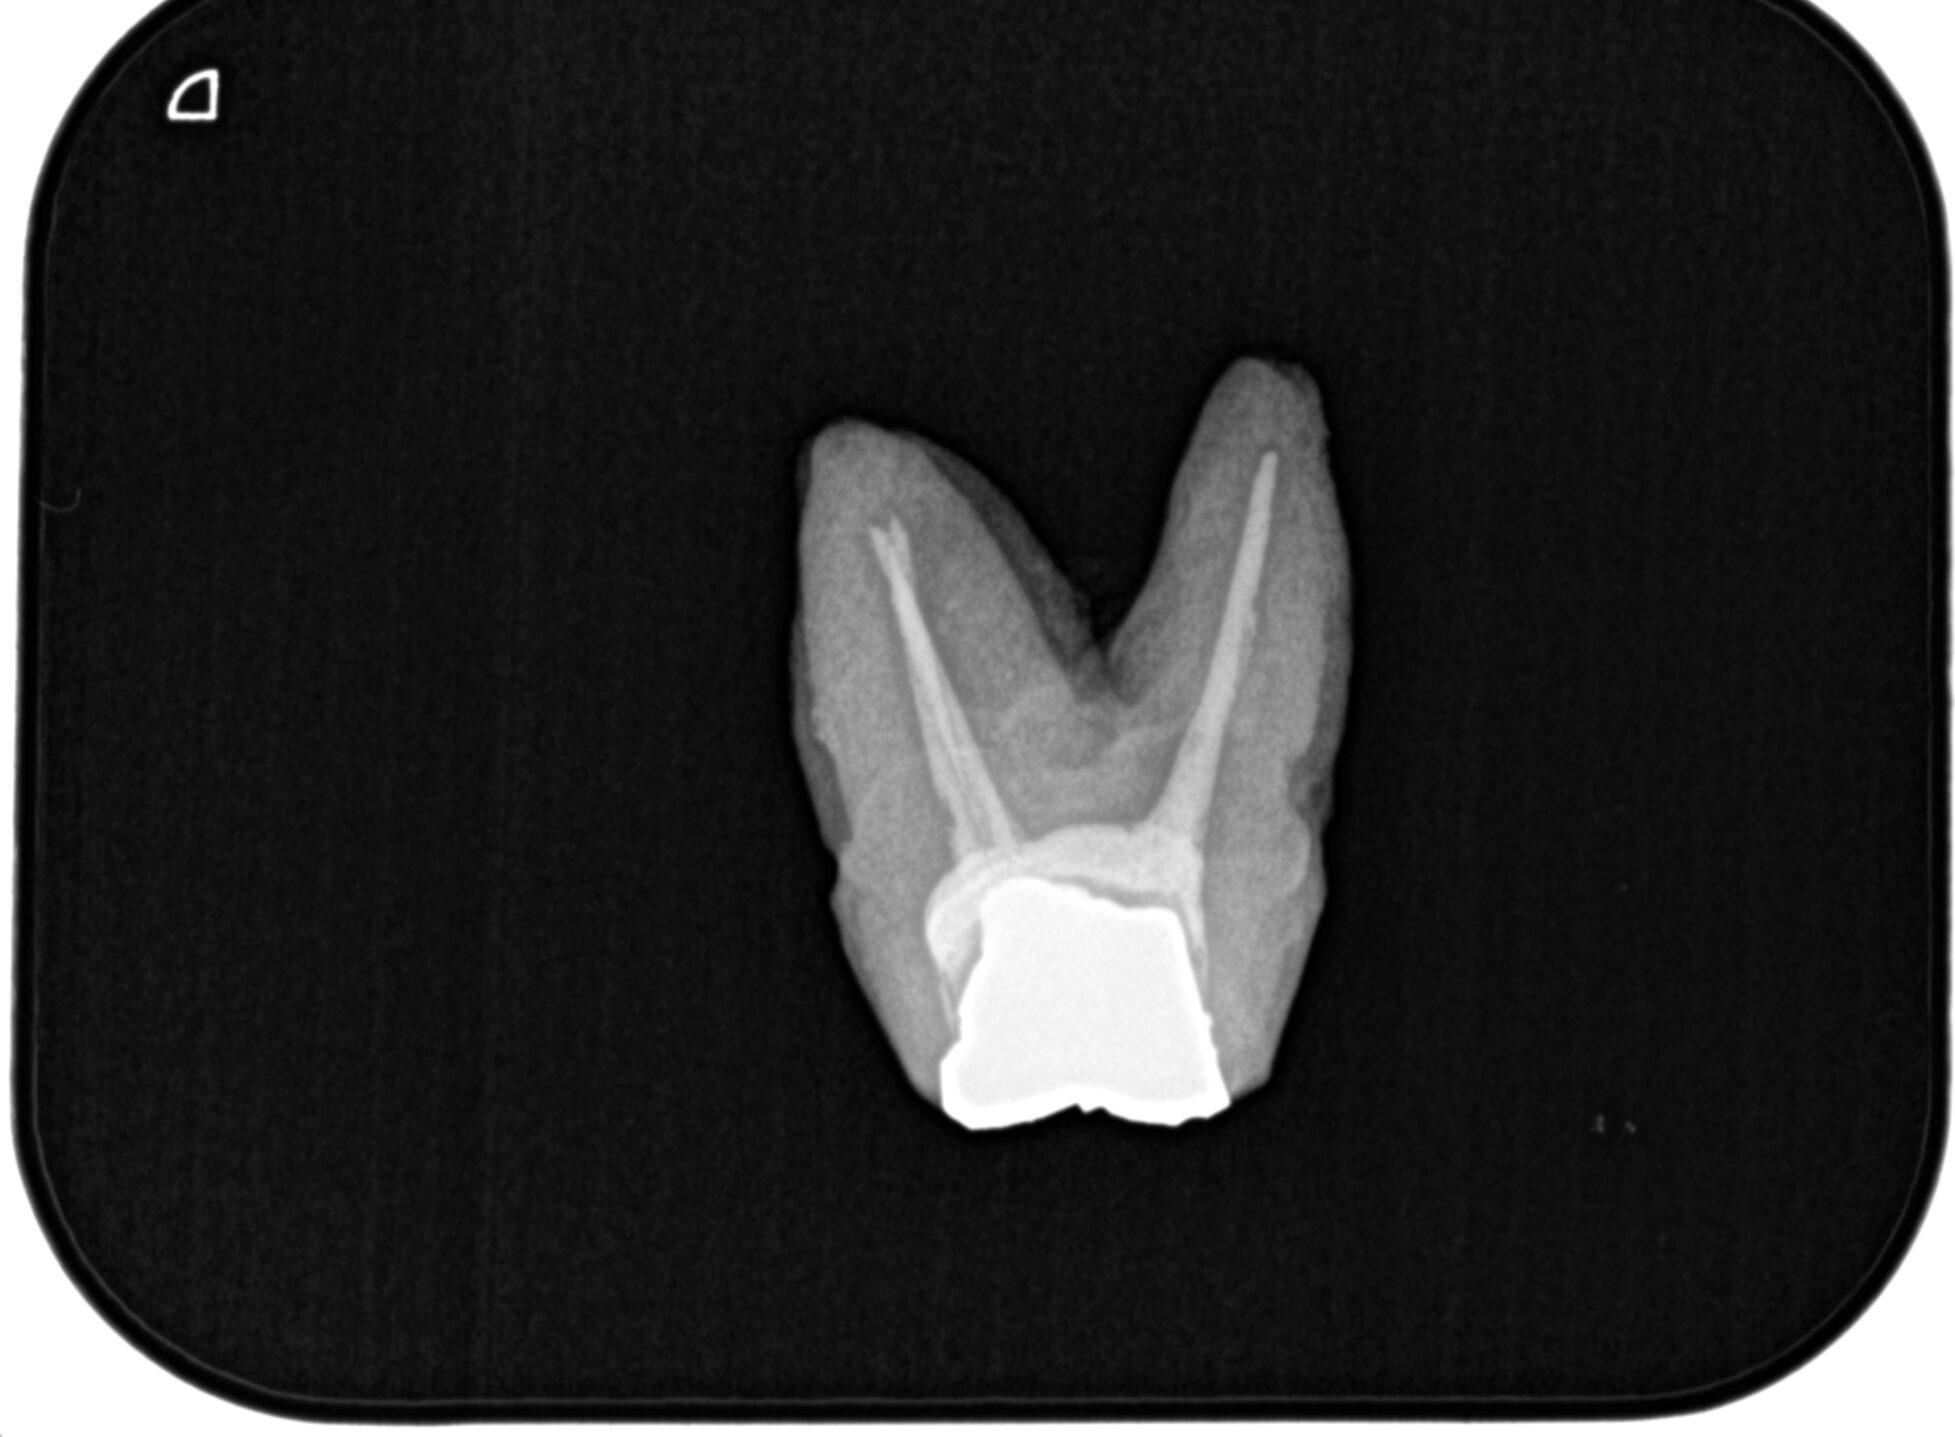

実習はまずメタルポストコアを外していただいた。

その際に必要な手技を直接お伝えした。

ポイントはやはり道具と考え方だろう。

すると、いとも簡単にメタルポストコアが次々脱離されていく。

今までの人生でそのようなことがなかったそうだ。

次がC-solutionによるGutta Percha Point除去である。